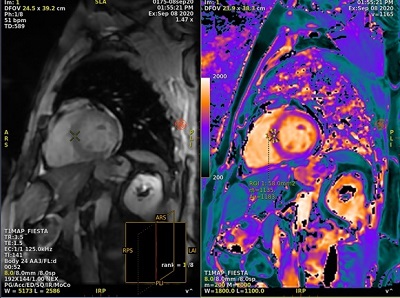

Motion Compensation with T1MAP scans

T1MAP with Motion Compensation scans provide better delineation of anterior and anteriolateral segments, which improves the accuracy of T1 estimates due to reduced motion artifacts.

For T1MAP scans, Motion Compensation corrects for small residual respiratory motion which may still be present during a breath hold scan. Therefore, acquire T1MAP scans during breath hold.

- T1MAP-SPGR with Imaging Option Motion Compensation

- T1MAP-Fiesta with Imaging Option Motion Compensation

Image reconstruction considerations

- The Motion Compensation preview images are displayed in AutoView while scanning but they are not stored in the Patient List. When displayed in AutoView, the series number is multiplied by 100. For example, if the original series is 2, the preview series, as displayed in AutoView, is 200.

Figure 5. AutoView series